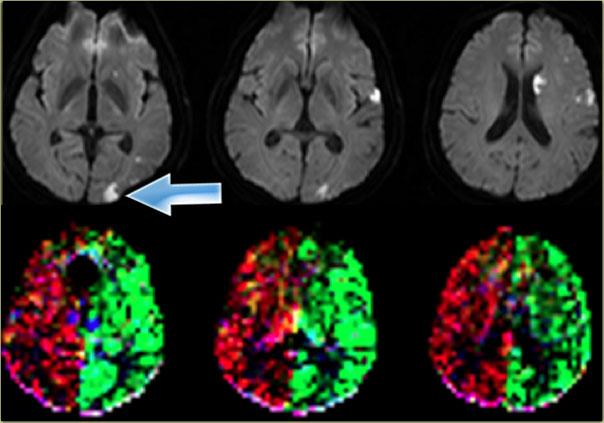

Bên trái là một biến thể khác trong tưới máu não ở bệnh nhân có nhiều ổ nhồi máu được ghi nhận trên hình ảnh khuếch tán (diffusion imaging).

Có một ổ nhồi máu vỏ não nhỏ ở thùy chẩm trái, vùng này được tưới máu bởi động mạch cảnh trong trái (mũi tên).

Lưu ý rằng hệ động mạch đốt sống-nền không tham gia tưới máu cho vùng này.